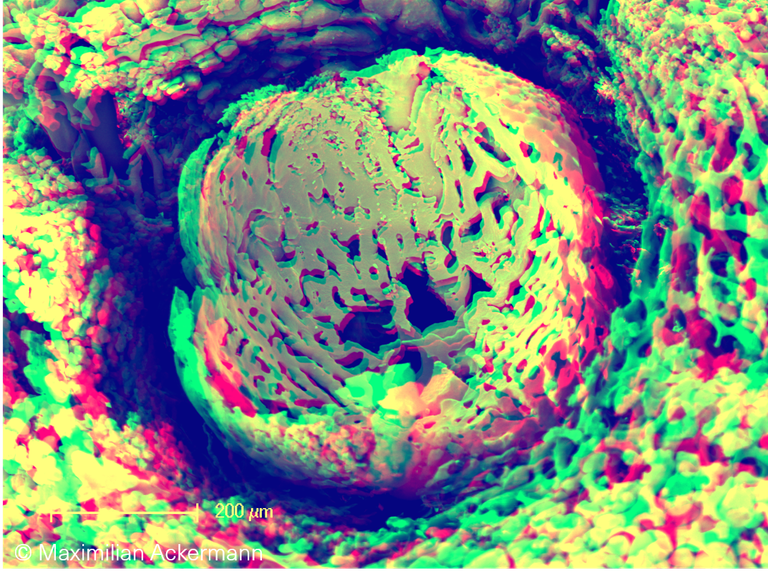

Eye development

Anaglyphic 3D SEM image of microvascular corrosion cast depicts the vascular branching by intussusceptive angiogenesis in the early development of the eye cavity.